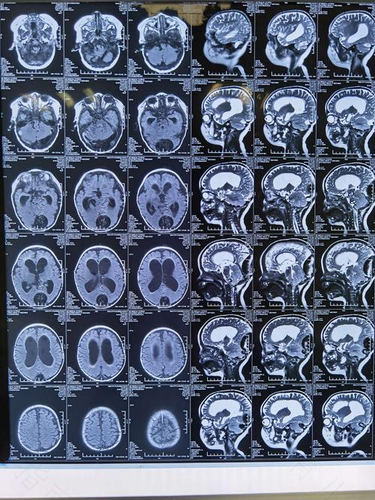

有脑积水首先要评估是属于哪一类型的,一般分为两大类,一种是交通性脑积水,在一个是梗阻性脑积水。不管是哪种的脑积水,都要注意,建议不要做剧烈的运动,因为运动过量回事我们的身体处于过于兴奋的状态在,这样很不利于有脑积水的患者。患有脑积水的人也不要吃过于辛辣的东西,不然也会加重病情。

脑积水术后要维持分流管通畅,还要注意观察有没有其他的发症。如果出现发烧,可能是感染,警惕分流管堵塞,内镜手术的做法,并发症相对较少,再次出现头疼和呕吐等,要警惕瘘口堵塞,尽快到医院进行检查就诊。饮食还要注意,不管是做什么手术,在手术后都要补充身体的营养,不然营养跟不上,身体就会恢复的慢。